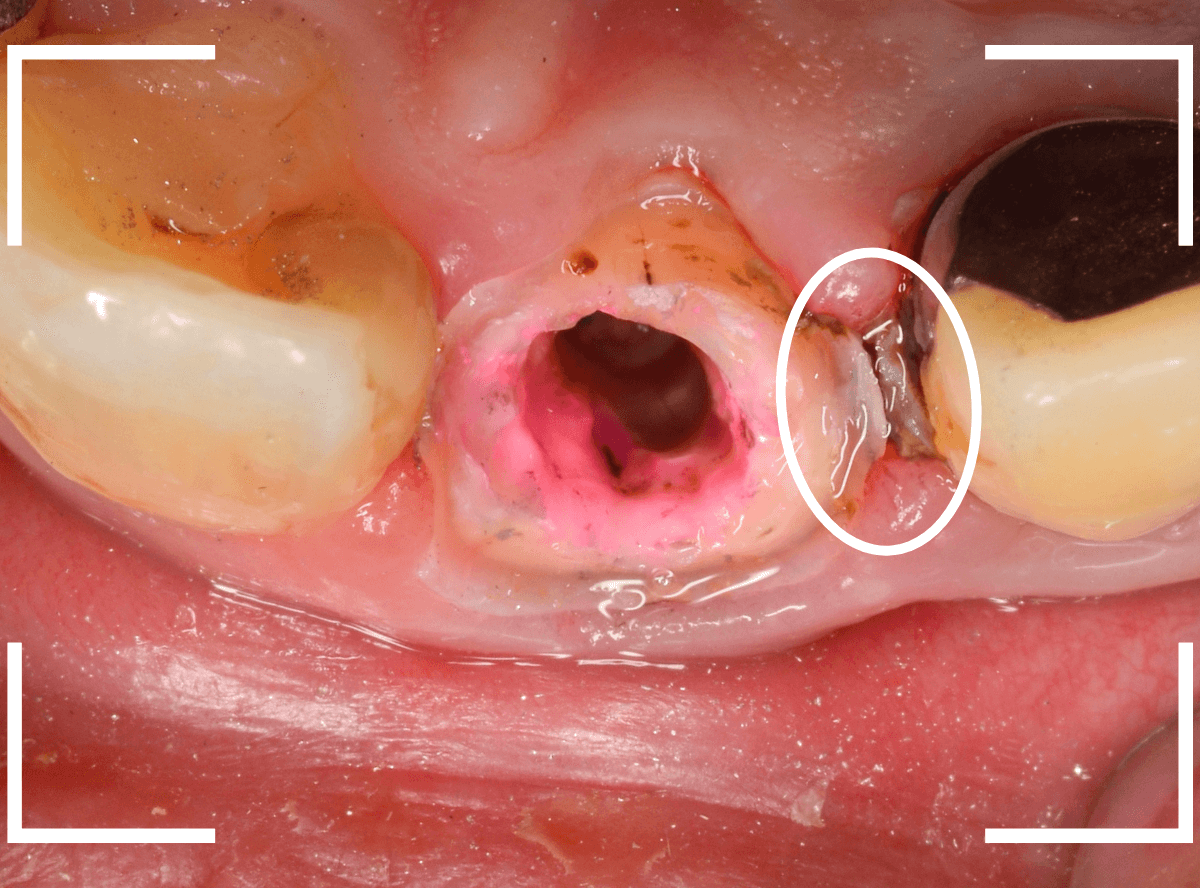

Case.5

さし歯の周りを歯石除去すると、血まみれになるのは何故?

今回は、さし歯の周りの歯周治療についてです。

〇部の前歯のさし歯ですが、隣の歯との形が不釣り合いな感じはありますが、見た感じそんなに問題はなさそうです。

しかし、さし歯の周りを軽く歯石除去をすると、たちどころに血まみれになってしまいます。

いったい何故でしょうか?

レントゲン写真で確認します。

隣のさし歯も、ですが、さし歯の縁が見えないところで不適合になっています。

これでは、いくら歯ブラシを頑張っても、汚れがたまってしまい、歯肉の改善ができません。

歯肉にぴったりあったさし歯に作り直す必要があります。

患者さんに状況を説明して、さし歯を外して確認します。

さし歯の中は、虫歯も進行しており、想像以上にひどい状況になっているのがわかります。

この状況では、いくら歯ブラシをしてもすぐにすき間に汚れがたまってしまうでしょう。

土台(メタル・コア)も外しつつ、虫歯を除去します。

赤く染色されている部分は虫歯です。

土台の中も虫歯になっていました。

早い段階で治療が出来てよかったです。

そして、後ろの歯との境の〇部には汚れや歯石が多くつまっています。

虫歯と共に、歯の周りの縁下歯石除去も行いました。

歯の周りがきれいになっているのがわかると思います。